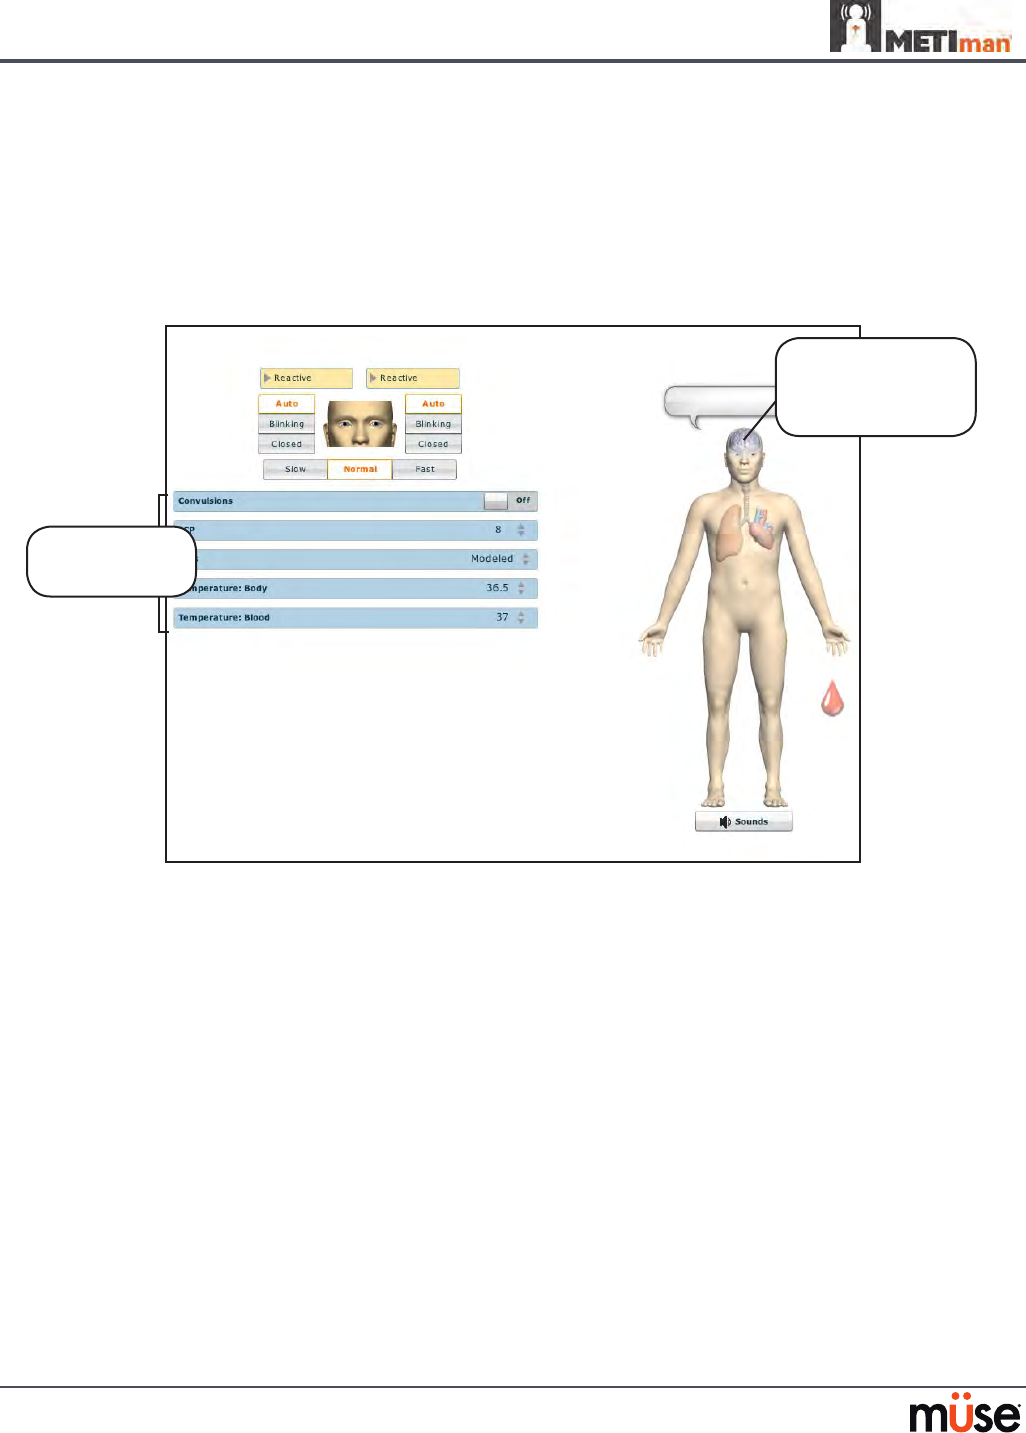

Neurological

The clinical features that can be controlled from the Neurological Assessment view

are Blinking Eyes, Reactive Pupils, Convulsions, Neuromuscular Block, Body and Blood

Temperature and Speech.

To access the Neurological view, from the Run screen, click the brain on the human form.

The Neurological View

Neurological

parameters

Click the brain

to access the

Neurological view

Eyes

The pupil diameter, pupil reactivity, blinking and blink speed of the simulator’s eyes can be

controlled from the software.

Click the Reactive drop-down menus of each eye to determine reactivity: Reactive, Non-

Reactive, Pinpoint or Blown.

Click Auto to have the eyes blink while the patient is conscious. Click Closed to close the eyes.

Click Blinking to force the eyes to be open and blinking regardless of patient consciousness.

These features can be controlled on both eyes.

Click Slow, Normal or Fast to control the blink speed.

Convulsions

METIman simulates convulsions when the feature is activated on the software. To activate

the Convulsions feature, click the Convulsions switch. The Convulsions feature is activated

when On appears. To deactivate the convulsions feature, click the switch again. The feature is

deactivated when O appears.

Neuromuscular Blockade

To manually adjust the Neuromuscular Blockade (NMB: Set), click NMB. The NMB slider

appears. Set the percentage by dragging the arrow up or down. Click Accept to exit and save

the changes.

Body Temperature

To control a patient’s body temperature, click Temperature: Body. The Body Temperature

slider appears. Set the body temperature by dragging the arrow up or down. Click Accept to

exit and save the changes.

Blood Temperature

To manually control a patient’s blood temperature, click Temperature: Blood. The Blood

Temperature slider appears. Set the temperature by dragging the arrow up or down. Click

Accept to exit and save the changes.